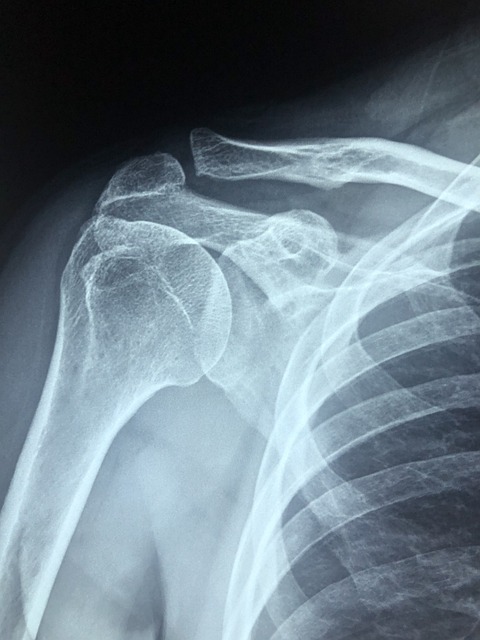

습관처럼 어깨가 빠지는 이유는? 만성 어깨 탈구의 원인과 해결법

어깨가 자주 빠지는 사람들에게는 공통된 해부학적, 유전적, 외상 후 요인이 있습니다. 습관적 어깨 탈구의 원인과 진단 기준, 치료 및 예방법을 전문가 관점에서 정리했습니다. 어깨 탈구, 왜 반복적으로 발생할까?어깨 관절은 우리 몸에서 가장 넓은 운동 범위를 가지는 관절이지만, 동시에 가장 불안정한 관절이기도 합니다. 이로 인해 어떤 사람들은 특별한 충격이 없어도 반복적으로 어깨가 빠지는 현상을 겪습니다. 이를 만성 또는 습관성 어깨 탈구라고 하며, 일상생활에 큰 지장을 줄 수 있습니다.이번 글에서는 어깨가 잘 빠지는 사람들의 특징과 그 원인, 의학적 진단 기준 및 치료법까지 폭넓게 정리하였습니다. 어깨 통증이나 반복적인 탈구로 고민하는 분들에게 실질적인 도움이 되길 바랍니다.어깨가 잘 빠지는 사람들의 공..